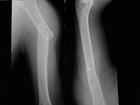

骨折後股骨矩的完整性未受到破壞,為穩定性骨折。股骨矩完整為不穩定型骨折。轉子進骨折有多種分類方法。參照Tronzo和Evans的分類分可將轉子間骨折分為五型:Ⅰ型,為單純轉子間骨折,骨折線由外上斜向下內,無移位。Ⅱ型,在Ⅰ型的基礎上,發生移位,合併小轉子撕脫骨折,但股骨矩完整。Ⅲ型,合併小轉子骨折,骨折累及股骨矩。有移位,常伴有準子間後部骨折。Ⅳ型伴有大、小轉子粉碎骨折,可出現股骨頸和大轉子冠狀面的爆裂骨折。Ⅴ型、為反轉子間骨折,骨折線由內上斜向下外,可伴有小準子骨折,股骨具破壞。

轉子間是骨質疏鬆的好發部位,骨質疏鬆的發生速度在骨小梁較快,在股骨矩則較慢,在發展速度快的骨下樑與發展速度慢的股骨矩的接合部是骨質最薄弱處,因此易發生轉子間骨折。受傷後,準子區出現疼痛,腫脹、淤斑、下肢不能活動,檢查發現轉子間壓痛,下肢外鏇畸形明顯,可達90度,有軸向扣痛,測量可發現下肢短縮。X線拍片可明確骨折的類型和移位情況。